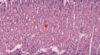

·So the endocrine functions, secretion into the blood, including storing glycogen and secreting it as glucose (see arrows), making albumin, fibrinogen, prothrombin – again, all kinds of interesting things, including IgF1.

·And also stores vitamin A, especially in those lipid droplets in the perisinusoidal cells